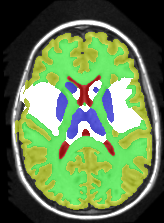

| ground truth | a-exp [7, 8] | QPBO [25, 8] | ours | |

In this application our method outperformed QPBO in most cases and a-exp in all cases. In fact a-exp always converged to a weak local minima in this setting, see Fig. 15. Based on our experience the quality of a-exp result depends on various factors, e.g. tree complexity, the number of min-margins introduced, the order in which labels are expanded, and the initial solution. For the subjects that QPBO was able to find the global optimal Path-Moves either found the global optimal or a very close solution.

Figure 16 shows the results for Subject 1 with (and without) min-margins and Hedgehog prior. The third row shows the results when not using min-margins. Path-Moves converged after two iterations to a lower energy than a-exp, which converged after six iterations. In this case a-exp local minimum was due to the Hedgehog prior, see last row.

Table 1 compares the precision, recall and F1 score for each region individually, where . The higher F1 values correspond to better segmentation. In general, QPBO was unpredictable as in some cases it found the optimal solution and in other cases it left a large number of pixels unlabeled.

Table 2 show the results after dropping the hedgehog prior. In terms of Path-Moves, the mainly affected label after dropping the Hedgehog prior is the sub-cortical gray matter, as it started to grab parts of the gray matter, see Fig.16 second row, last column. Comparing Tables 1 and 2 it is clear that QPBO and a-exp benefited the most by introducing the hedgehog prior.